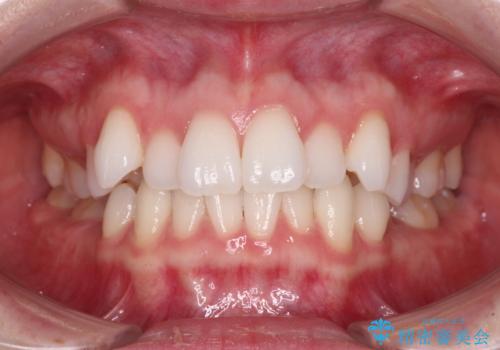

![[突き出た前歯を引っ込めたい] ワイヤー矯正とマウスピース矯正の併用治療の症例 治療前](https://seimitsushinbi.jp/wp/wp-content/uploads/2024/08/IMG_0066-500x350.jpg?v=1723179360)